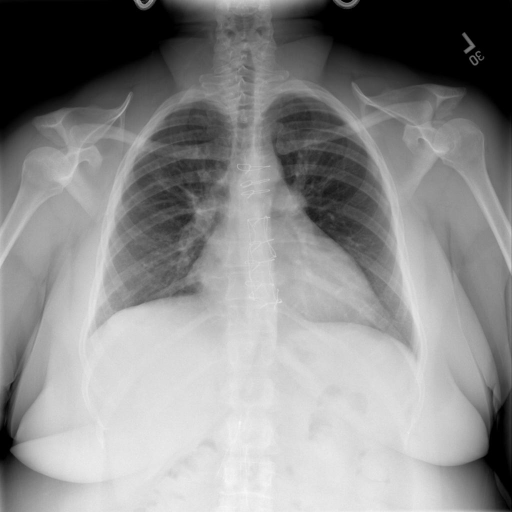

# 本文贡献  - 借助ChatGPT以及公开的数据集,我们构造了一个`X光影像-诊断报告`对的医学多模态数据集; # 数据集 - [MIMIC-CXR](https://physionet.org/content/mimic-cxr-jpg/2.0.0/)是一个公开可用的胸部X光片数据集,包括377,110张图像和227,827个相关报告。 - [OpenI](https://openi.nlm.nih.gov/faq#collection)是一个来自印第安纳大学医院的胸部X光片数据集,包括6,459张图像和3,955个报告。 在上述工作中,报告信息都为非结构化的,不利于科学研究。为了生成合理的医学报告,我们对两个数据集进行了预处理,并最终得到了可以用于训练的**英文报告**。除此之外,为了更好的支持中文社区发展,借助ChatGPT的能力,我们将英文报告进行了中文翻译,并最终形成了可用于训练的数据集。 |数据集|数量|下载链接| |:-|:-|:-| |MIMIC-CXR-zh|-|-| |OpenI-zh|6,423|[诊疗报告](./data/Xray/openi-zh.json) 、[X光影像](https://pan.baidu.com/s/13GBsDMKf6xBZBSHpoWH_EA?pwd=k9sh)| # 快速上手 1. 安装环境 ```bash # 安装依赖 pip install -r requirements.txt # 国内换源安装依赖 pip install -i https://mirrors.aliyun.com/pypi/simple/ -r requirements.txt ``` 此时默认会安装`deepspeed`库(支持`sat`库训练),此库对于模型推理并非必要,同时部分`Windows`环境安装此库时会遇到问题。 如果想绕过`deepspeed`安装,我们可以将命令改为: ```bash # 安装依赖 pip install -i https://mirrors.aliyun.com/pypi/simple/ -r requirements_wo_ds.txt # 安装SwissArmyTransformer pip install -i https://mirrors.aliyun.com/pypi/simple/ --no-deps "SwissArmyTransformer>=0.3.6" ``` 2. 模型推理 # 效果展示 |X光影像|诊疗报告(医生)|XrayGLM| |:-|:-|:-| ||根据X射线图像,心脏大小正常,肺部看起来很清晰。已经排除了肺炎、积液、水肿、气胸、腺病、结节或肿块的存在。该发现表明一切正常。换句话说,总体印象是胸部正常。|X光片显示,心脏大小正常。肺部没有气胸或胸腔积液的证据。骨骼结构看起来没有任何异常。总的来说,X光片表明没有发现急性心肺疾病的 迹象。| # 项目致谢 1. [VisualGLM-6B](https://github.com/THUDM/VisualGLM-6B)为我们提供了基础的代码参考和实现; 2. [MiniGPT-4](https://github.com/Vision-CAIR/MiniGPT-4)为我们这个项目提供了研发思路; 3. ChatGPT生成了高质量的中文版X光检查报告以支持XrayGLM训练; 4. [gpt_academic](https://github.com/binary-husky/gpt_academic)为文档翻译提供了多线程加速; 5. [MedCLIP](https://github.com/RyanWangZf/MedCLIP) 、[BLIP2](https://huggingface.co/docs/transformers/main/model_doc/blip-2) 、[XrayGPT](https://github.com/mbzuai-oryx/XrayGPT) 等工作也有重大的参考意义;  这项工作由[澳门理工大学应用科学学院](https://www.mpu.edu.mo/esca/zh/index.php)硕士生[王荣胜](https://github.com/WangRongsheng) 、[段耀菲](https://github.com/IsBaSO4) 、[李俊蓉](https://github.com/lijunrong0815)完成,同时这项工作受到[檀韬](https://scholar.google.com/citations?hl=zh-CN&user=lLg3WRkAAAAJ)副教授、[彭祥佑](http://www.patrickpang.net/)老师的帮助支持。 *特别鸣谢:[USTC-PhD Yongle Luo](https://github.com/kaixindelele) 提供了有3000美金的OpenAI账号,帮助我们完成大量的X光报告翻译工作 # 免责声明 本项目相关资源仅供学术研究之用,严禁用于商业用途。使用涉及第三方代码的部分时,请严格遵循相应的开源协议。模型生成的内容受模型计算、随机性和量化精度损失等因素影响,本项目无法对其准确性作出保证。即使本项目模型输出符合医学事实,也不能被用作实际医学诊断的依据。对于模型输出的任何内容,本项目不承担任何法律责任,亦不对因使用相关资源和输出结果而可能产生的任何损失承担责任。 # 项目引用 如果你使用了本项目的模型,数据或者代码,请声明引用: ```bash @misc{wang2023XrayGLM, title={XrayGLM: The first Chinese Medical Multimodal Model that Chest Radiographs Summarization}, author={Rongsheng Wang, Yaofei Duan, Junrong Li, Patrick Pang and Tao Tan}, year={2023}, publisher = {GitHub}, journal = {GitHub repository}, howpublished = {\url{https://github.com/WangRongsheng/XrayGLM}}, } ``` # 使用许可 此存储库遵循[CC BY-NC-SA](https://creativecommons.org/licenses/by-nc-sa/4.0/) ,请参阅许可条款。